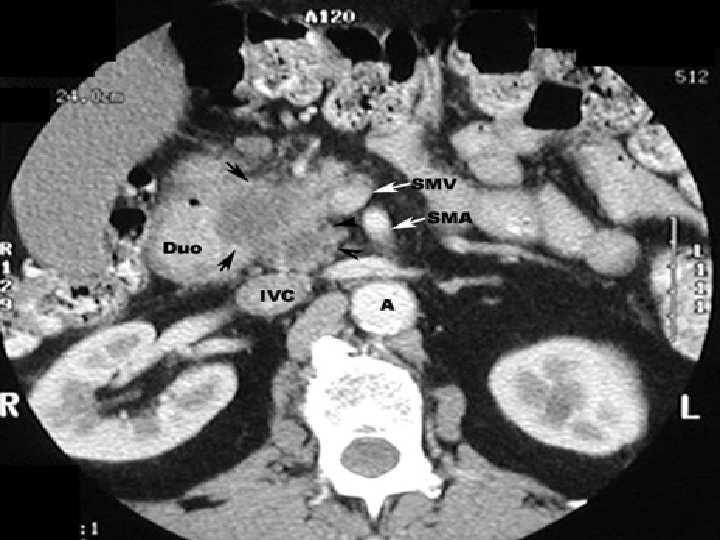

1. l’échographie abdominale: - peut déceler une tumeur pancréatique hypoéchogène supérieure à 2 cm - peut montrer une dilatation des voies biliaires, de la vésicule ou une dilatation du Wirsung - déceler: ascite, ganglions, métastases 2. L’écho-endoscopie: - détecte des lésions inférieures à 2 cm - précise l’extension loco-régionale: envahissement des vaisseaux porte ou mésentérique - permet une cyto-ponction (qui n’a de valeur que si positive) 3. TDM et IRM +++: - détecte les masses hypodenses focales ou diffuses - et les signes indirects +++: dilatation biliaire, du Wirsung, atrophie parenchymateuse d’amont

Cancer tête, corps queue du pancréas

Le traitement curatif est chirurgical, mais seulement 15% des cancers du pancréas sont résécables. Les principales contre-indications sont: - âge physiologique avancé - cachexie - carcinose, métastases hépatiques, Troisier - envahissement veineux (tronc porte, veine mésentérique supérieure) ou artériel - métastases ganglionnaires